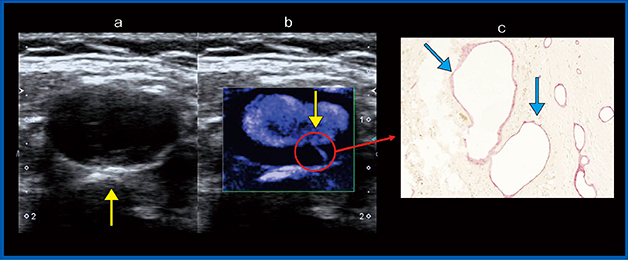

症例3は,73歳,男性。症候性プラークの症例で,Bモード(図5a)では全周性に低輝度のプラークを認めた。SMI(図5b)では,内頸動脈と外頸動脈の分岐部分に,縦に走る血流が認められた(↓)。症候性で狭窄があったことからCEAを施行し,剥離切除した検体に対して血管内皮細胞のマーカーであるCD34を用いた免疫染色を行ったところ(図5c),SMIで描出されたのと同じ部分に,比較的大きな新生血管(↓)が認められた。病理標本の結果とSMIで描出された血流の部分が一致した症例である。

図5 症例3:症候性の頸動脈プラーク

a:Bモード画像,b:SMI画像,c:病理画像(CD34染色×100)